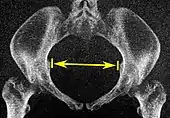

Pelvic inlet Transverse diameter of the pelvic inlet

Coronal plane

The iliopectineal lines, at widest transverse distance.13 to 14.5 cm.[4]